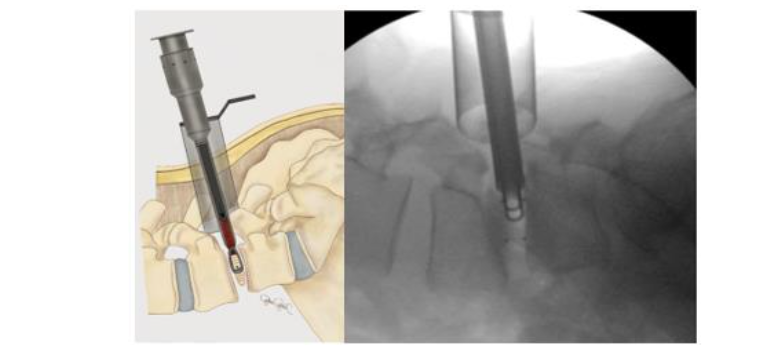

With the implant positioned properly within the disc space, BoneBac TLIF bullets are filled with morselized autograft collected from the BoneBac Press which are then loaded on top of the implant inserter T-handle, and the morselized bone graft material is pushed through the implant holder using a plunger to exit either side of the PEEK cage within the disc space (Figures 8 and 9). Typically, 10–15 bullets are used to completely fill the disc space with morselized autograft. Each bullet contains about 1.5 cc of bone graft material. If additional graft material is needed, 1–5 ccs of morselized allograft (Trinity Elite, Orthofix, Lewisville, TX) or other suitable bone graft extender is mixed with morselized autograph bone graft material. The system allows for adequate quantity of bone to be injected into the interspace to ensure compression of graft material rather than the implant itself, thereby reducing the incidence of implant subsidence and improving arthrodesis rates. After the disc space is sufficiently filled with graft material, the implant is disengaged in the disc space which is then inspected using microscope visualization and a ball-ended probe to ensure that the bone graft material is entirely within the disc space. The facet complex is then reconstructed using a combination of morselized autograft mixed with allograft material.

PERCUTANEOUS PEDICLE SCREW INSTRUMENTATION

Once adequate decompression, interbody placement and complete hemostasis are achieved, the tubular retractor is removed, and an incision is made on the contralateral side, equidistant from the midline (3 cm), for the interbody fusion. AP and lateral fluoroscopy are used to target the pedicles for percutaneous pedicle screw fixation and place initial K-wires. Once the K-wires are placed they are then stimulated with concurrent neuromonitoring. A stimulation threshold less than 8 mAmps requires repositioning of K-wire or later pedicle screw. Percutaneous pedicle screws are placed bilaterally and segmentally to ensure suitable fixation to promote arthrodesis.

Total reduction of spondylolisthesis is performed by securing the rod to the most dorsal pedicle screw head (i.e., L5 seen in L4–5 spondylolisthesis) (Figure 10) and subsequently bringing the ventral pedicle screw head up towards the rod (Figure 11). This is done simultaneously bilaterally to reduce rotation and achieve total spondylolisthesis reduction thus restoring sagittal alignment. The advantages of this technique specifically arise from significant increases in the diameter of the neural foramen and spinal canal, and the larger surface area for fusion between adjacent vertebrae. The unique design of the PEEK Thompson MIS BoneBac TLIF device, with curved ends that correspond to the vertebral endplates, helps to facilitate reduction of the spondylolisthesis (Figures 10 and 11). Final tightening is performed, and the towers are removed allowing the paraspinous muscles to return to their normal anatomical position. Excellent long-term clinical outcomes and fusion rates using the MI-TLIF technique described have been achieved (Figures 13 and 14). More recently, but not within the patients covered in this data set, we began trialing augmented reality image guided navigation to place percutaneous pedicle screws in an effort to further reduce radiation exposure to both the patient and surgical team (Figure 15).